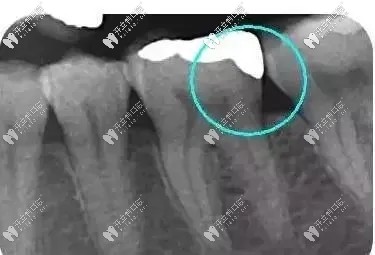

從下面這張X線中可以看出,嵌體遠中邊緣沒有懸突,與牙體邊緣密合相接。

牙齒嵌體拍片圖示